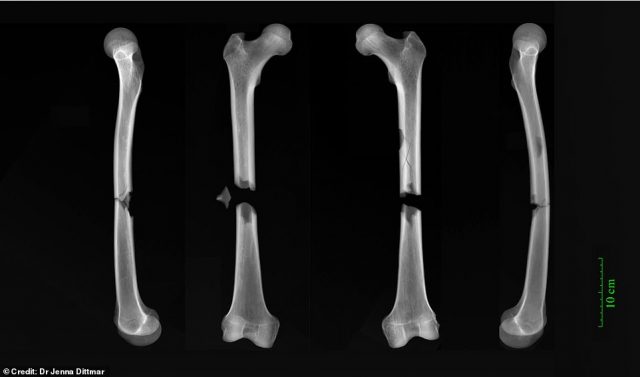

Nowhere is this more apparent than in the worst example, the sorry remains of a friar. He suffered 2 snapped femurs, which almost certainly resulted in his demise. What caused the agonizing blow? “Our best guess is a cart accident” Dr Dittmar told The Times. The result is also compared to being hit by a car.